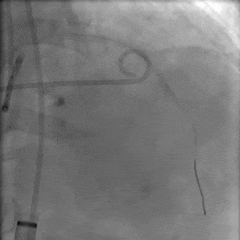

第一次释放,瓣膜位置偏高,选择回收

第二次瓣膜释放

造影评估,瓣膜位置可

右侧位造影,瓣膜深度可

多角度评估,瓣膜位置可,少量瓣周漏